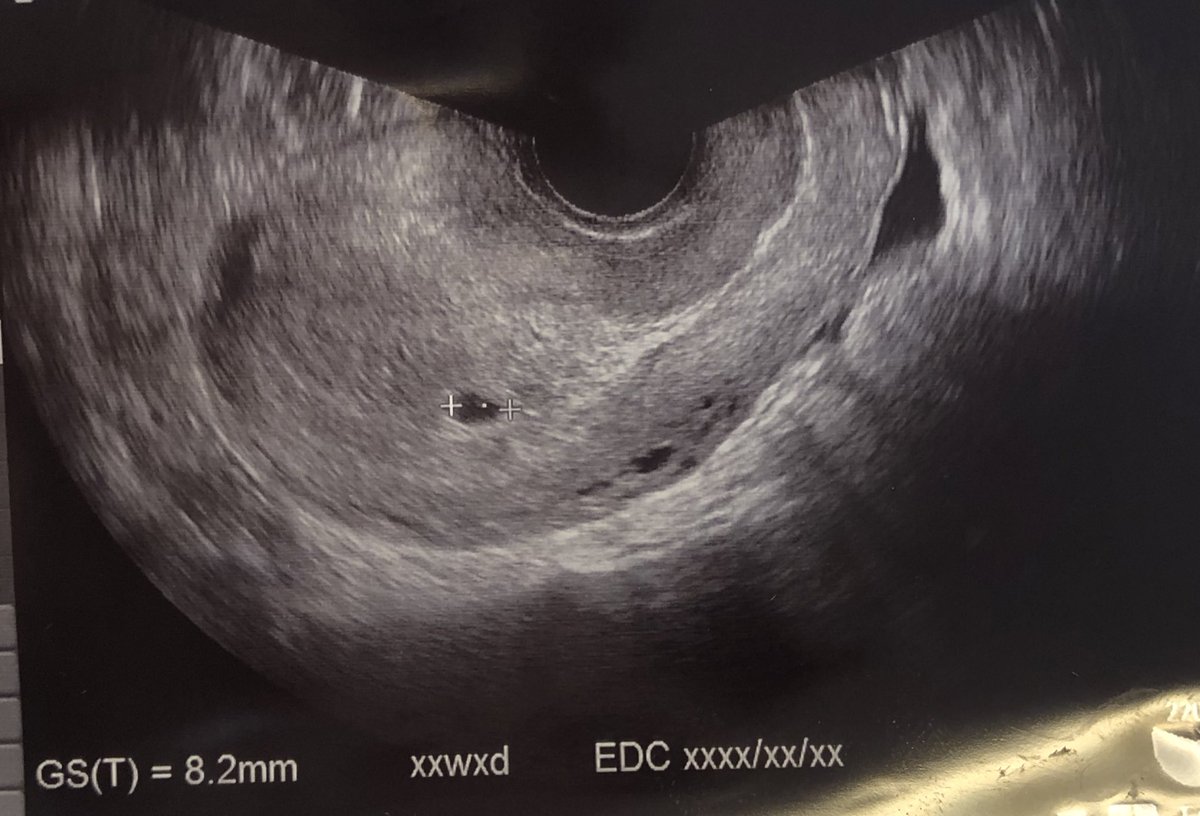

BT17 胎嚢小さい? 妊娠週数だと5週1日です。 胎嚢は4ミリ。 と言われたので悪い予感がして、待合室で胎嚢の大きさを検索。 小さい明らかに小さい。 「胎嚢確認出来ましたね。 では次の診察は一週間後の~」 とまたサッサと話が進んでいくので、慌てて「胎嚢小さくないですか? 」と質問し胎嚢確認bt17/klc16 40歳「ドリー」の女の子ママ ︎育児生活ブログBT17 とくに症状なしです BT16の5w0d 胎嚢が見なかったので 普通の胎嚢のサイズを探してみました! それっぽい研究資料ををみつけたのでそこから 胎嚢の大きさ 4w2d →15mm

胎嚢確認できて良かった という安心感はあったけれど、 なんとなく大きさが気になってネットで検索しちゃうとね、 女医先生は「順調」って言ってくれたけれど、 前も5W6Dで9.8mmの胎嚢が · BT17 胎嚢確認 5w1d まずは数値から↓ E2 2267 P4 06 βHCG この日、朝茶色い出血があり焦る。 茶色だけど出血は出血どきどきしながら病院へ行きました。 結果、HCGが驚きの伸びを見せてくれました! そして胎嚢も無事確認!サイズは58mmと小さめ。 ネットでいろいろ見てると大きさが心配になるものの、とりあえずホッとしました 出血については、茶色胎嚢は、62mmでした。 夢クリの基準値(BT17)が510mmとの事でしたので BT18の判定という事を考慮すると かなりギリギリの数値ではありますが (この時期胎嚢は1日1mm成長) 何とか基準値内はクリアしてくれました。 先生からは

· bt17胎嚢確認診察。大きさやe2が平均値より低いのが気がかり。 18年3月21日 ホルモン補充移植周期bt22の「成長・ホルモン値評価」に行ってきました。 nacのプリントによると、週数は5w6d。 (bt22診察は、経過により診察なしの方もいるようです) 前回のbt17胎嚢確認で寺元先生が、 「次回心拍 · 平均5人が回答 50以上の診療科の医師 医師に相談する トップ カテゴリ一覧 妊娠・出産 高齢出産 5w1d,BT17の胎嚢の大きさについて close 無料公開について 会員限定Q&Aのうち、どなたでも医師回答を見られる直近14日間に投稿された相談です。 全250万件の本人認証済みの医師が答えるQ&Aは正常(平均27mm)と 流産(平均26mm)であまり違いが見られません。統計的にも違いなし。 つまり、5週0日までは胎嚢のサイズを気にする必要なし! 次に5週1日~6週0日(36日から42日)を見てください。 正常の平均mm、 流産の平均45mm。統計的にも違います。

· 今回3回目のicsiでようやく陽性判定をもらい、 昨日5週1日でエコーでしたが胎嚢が6mmでした。 凍結胚盤胞移植なので日数に狂いはありません。 医学書やネット公開の胎嚢の大きさをみてると 5週1日は10mmくらいが平均のように思います。 以前AIHでやはり心拍確認前に2度流産しており 不安で不安でたまりません・・。 ジネコの書庫検索しましたが 週数に比べて · BT17 胎嚢 77mm BT17の夢クリ基準値が510mmという事でしたので 77mmであれば、普通では?とも思いましたが 診察室でも先生は 『 やや小ぶりですが胎嚢が確認出来ました 』 と。。。 やや小ぶり。。。やはり小さめという見解の様子。 BT17の胎嚢サイズについて質問してみましたところ 『 1cm位は胎嚢の直径は約10~25mmで10後半mm前後が平均です。 胎芽は妊娠6週後半になると6mm程度になります。 妊娠7週の⼤きさ 胎嚢の直径は15~35mm程度と個人差が大きくなり、平均約25mmです。 胎